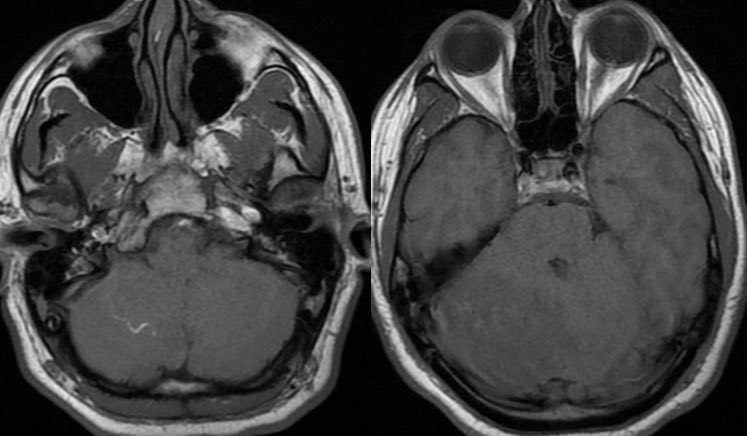

MRI: Enlarged or swollen right cerebellar hemisphere

T1: Hypointense with curvilinear high signal (slow flow in vessels)

T2: multiple tortuous flow voids and extensive edema but PRESERVED FOLIA

T1C+: bizarre somewhat geographic enhancement of the parenchyma and leptomeninges

▶️DWI: No diffusion restriction

▶️SWI: patchy areas of hemorrhage and engorged vessels